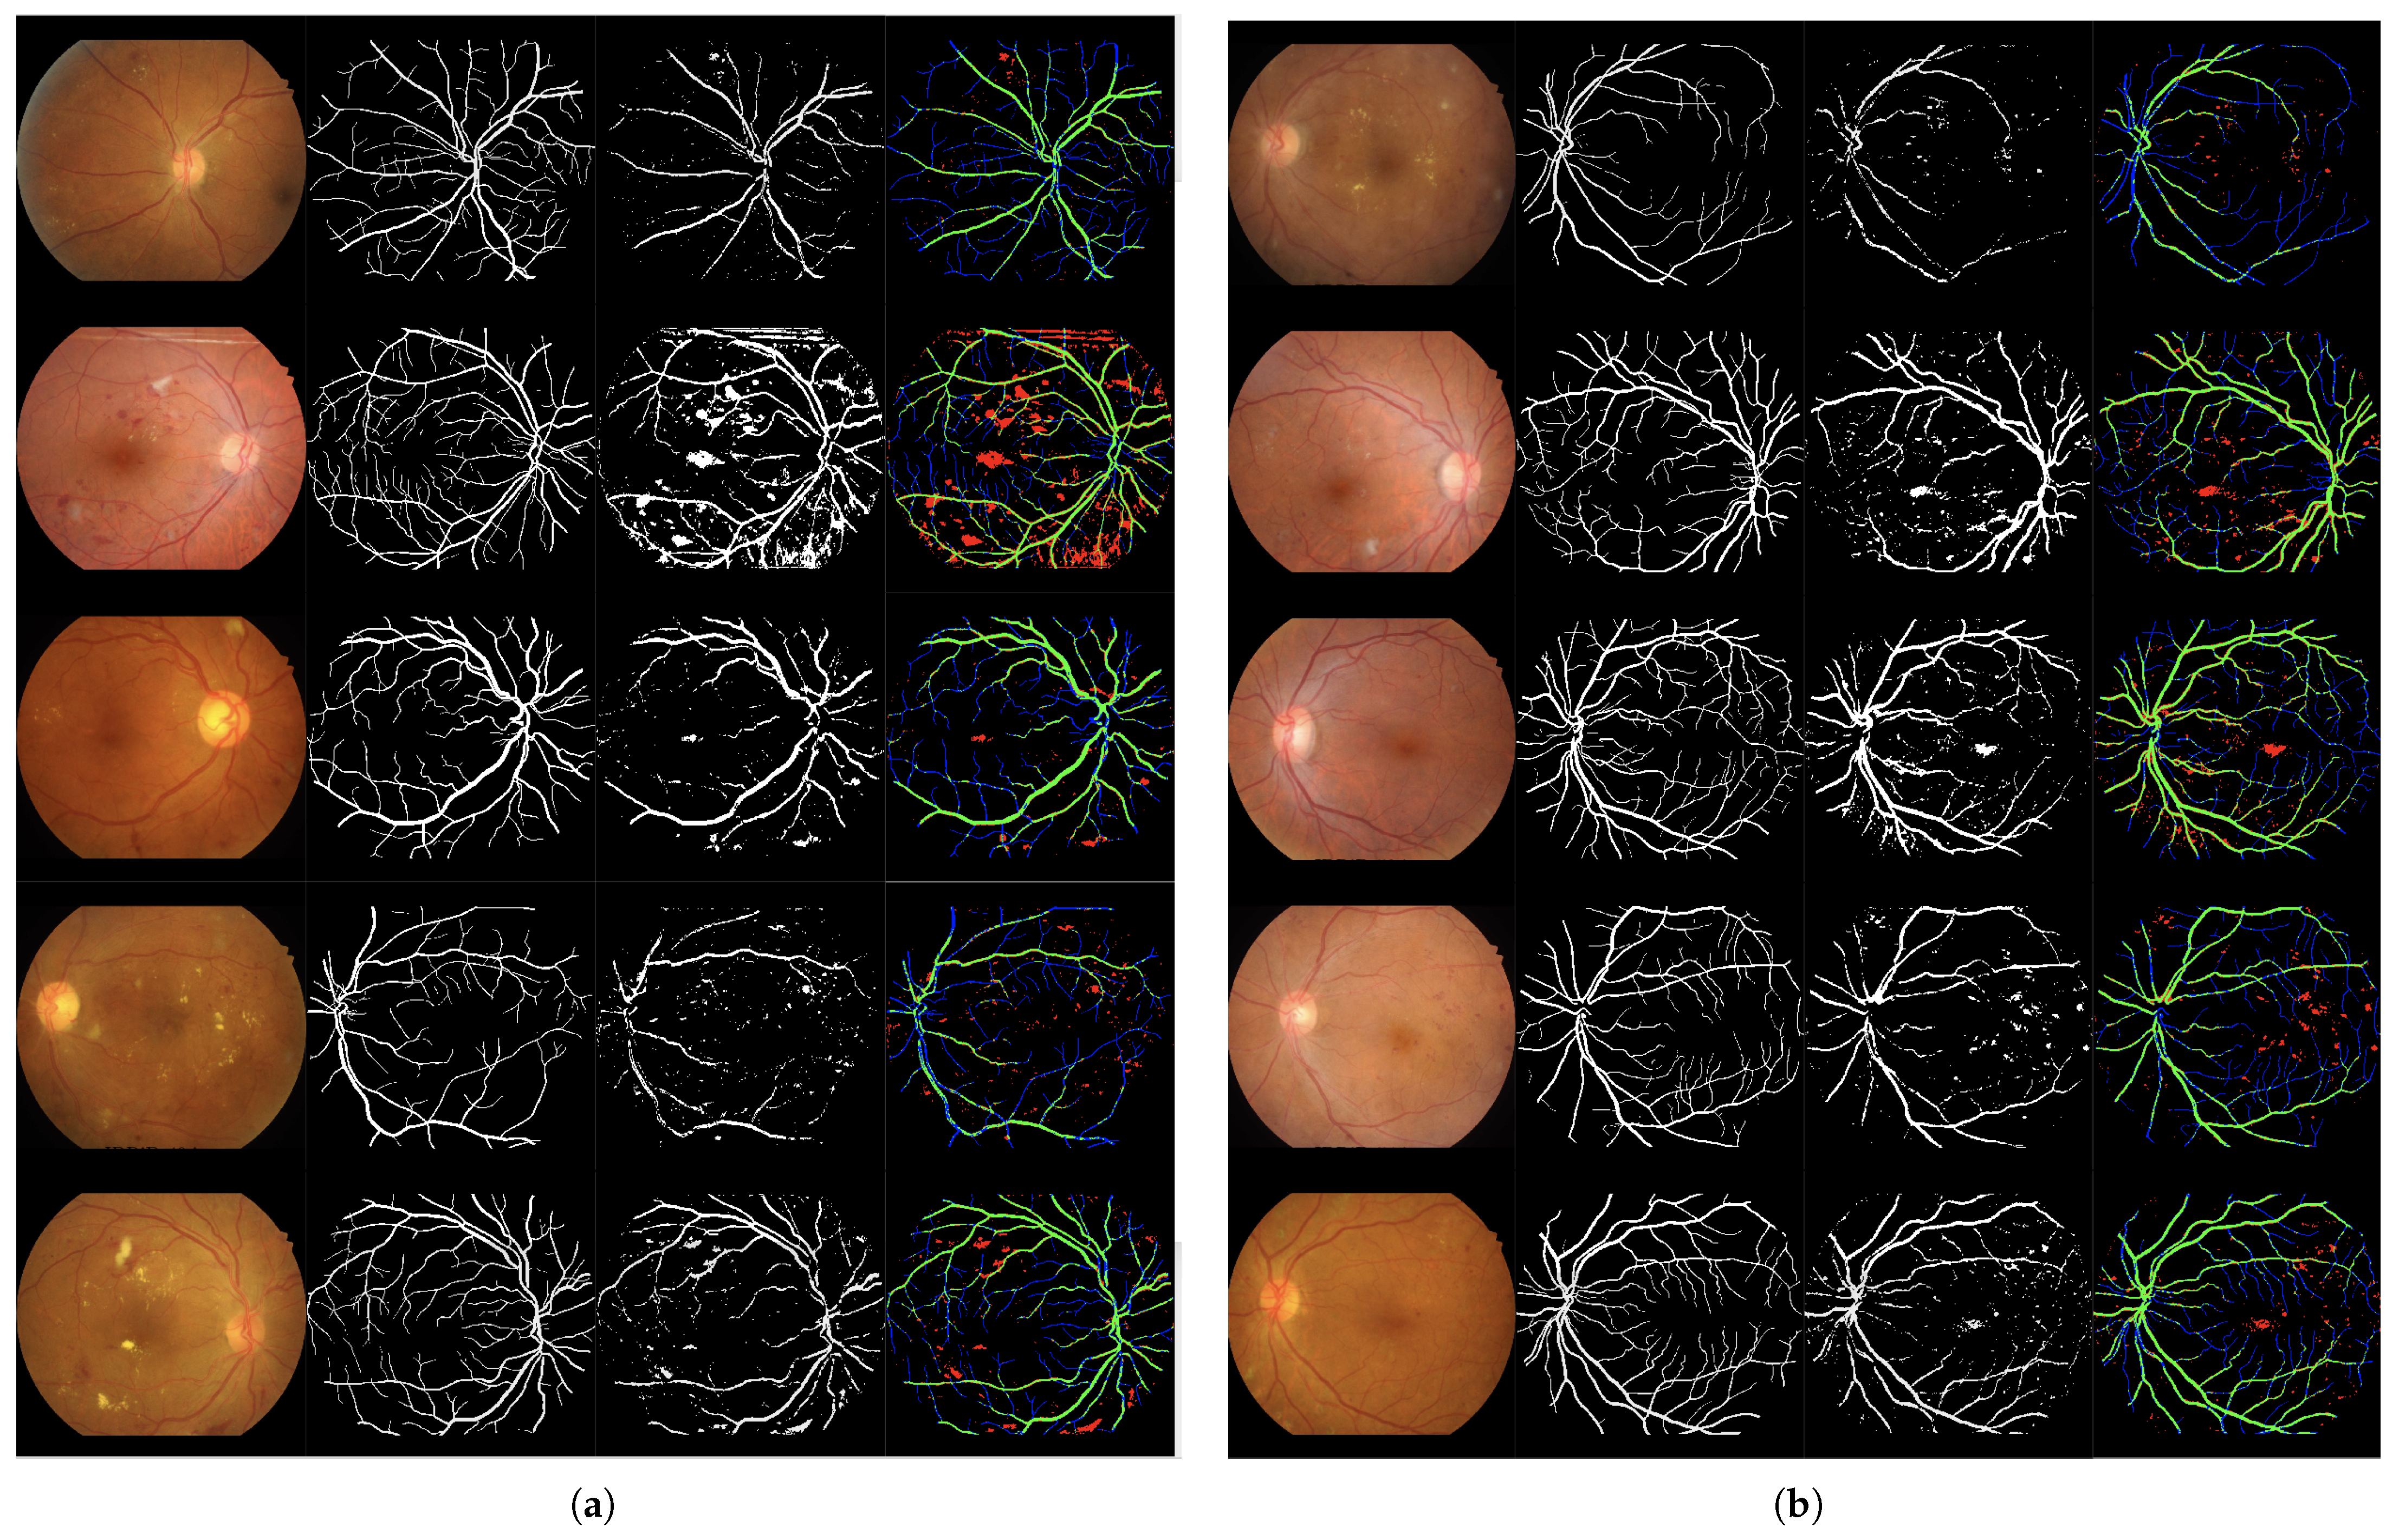

Figure 5.

Set of 4-image sequences illustrating the test results of Experiment 1 graphically. The first image is the original input, the second shows the ground truth vessel locations labeled by experts, the third corresponds to the output of the ANN from experiment 1, and the fourth visualizes the outcome in terms of true positives (green), false positives (red), false negatives (blue), and true negatives (black). Panel (a) displays the first five test images, while panel (b) shows the last five.